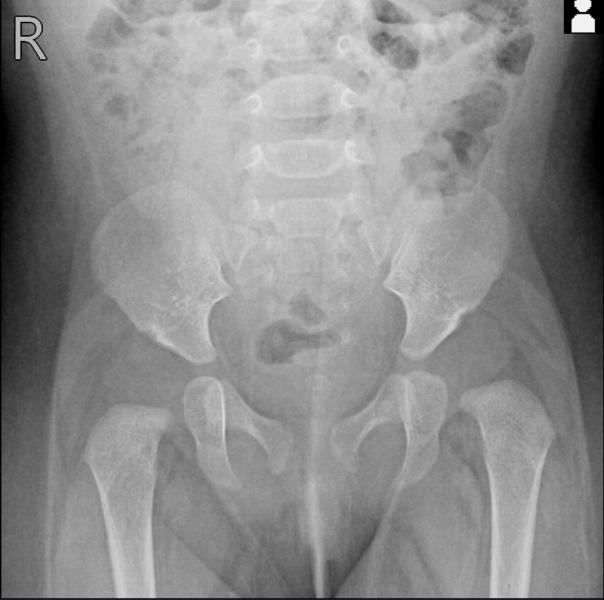

Малышке почти 5 месяцев,нам ставят подвывих,дисплазия обоих суставов. Прием только в субботу,ортопед,который предположительно поставил диагноз советовал обратиться в 1000 коечную. Подскажите пожалуйста,кто с таким диагнозом обращался туда? Они берутся за лечение и как это выглядит? Дневной стационар или домашнее лечение,понятно зависит от случая,просто интересно послушать…

Благодарю 🙏 1.11 запись,жду скорее,очень волнительно. Там просто мнение озвучат,диагноз по рентгену уже очевиден… Физио и другие манипуляции в любом случае при поликлиники наверное либо при стационаре 🤔

@treflik меня вообще удивляют врачи, которые дисплазию ставят без рентгена🫣